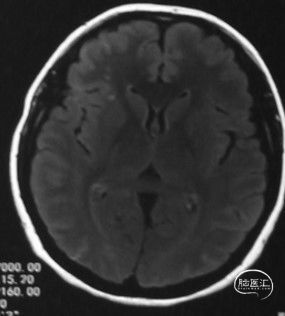

病人甲的影像资料:

T2 Flair:左侧额顶叶脑软化灶,右侧内分水岭区腔梗;

弥散:阴性;